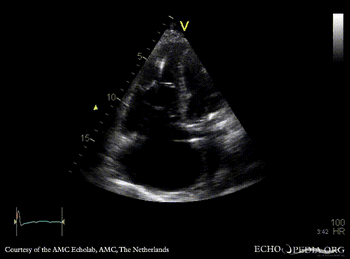

| A4CH: coronary sinus a vue